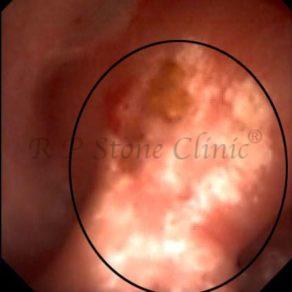

Kidney stone is a solid mass of CRYSTALS. It is the process of crystallization which initiates the formation of kidney stones. This happens in nephrons or units of kidney. Once a small crystal is formed, it can both grow & unite with other crystals leading to the formation of small concretion which eventually forms a stone. Once these large crystals detach from the collecting ducts, the process of stone formation starts in the renal collecting system. A recurrent kidney stone former is advised to know a little bit about something known as Randall’s plaque. Alexander Randall discovered plaques on the renal papillae eight decades back based on examination of 1154 pairs of autopsied Kidneys. He described these renal papillary lesions as cream colored or milk patch areas composed of calcium phosphate & calcium carbonate. These plaques could act as NIDUS for formation of KIDNEY STONE. Calcium Oxalate stone can form on this nidus & then detaches from this plaque to become a free floating stone in the collecting system of kidney

These images are taken as snap shots from the video recording of RIRS Surgery done at our hospital. These are Randall’s Plaques seen with Digital FLEX XC & Digital FLEX XC S. The cream or whitish patches are seen on the tips of RENAL PAPILLAE as seen in images below.

Randall’s Plaques may lead to the formation of Stones.